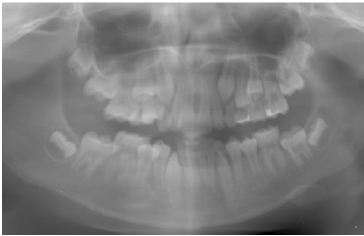

At the subsequent follow-up appointment in February 2023, when the patient was 11 years old, she returned for further evaluation. All diagnostic test results were within normal ranges, and routine systemic examinations were unremarkable. Clinically, she demonstrated normal physical development and age-appropriate dentition, with no systemic abnormalities. In the mandibular anterior region, localized labial bone resorption was noted around the permanent central incisors, accompanied by buccal gingival recession measuring approximately 3 mm. The gingival tissues appeared otherwise healthy, without bleeding or inflammation, and no abnormal mobility of the incisors was detected. Mild anterior crowding was evident in both maxillary and mandibular arches; however, no significant malocclusion, such as a crossbite or open bite, was observed. A panoramic radiograph confirmed the clinical findings, showing localized alveolar bone loss limited to the mandibular central incisors, while the remaining dentition followed a normal eruption sequence for the mixed dentition stage (Fig. 3).

Panoramic radiograph at age 11 (2023), confirming localized alveolar bone resorption in the mandibular central incisors, with the remaining dentition showing a normal eruption.